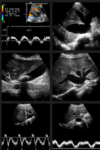

# Abdome: doença hepática difusa **Hepatopatia congestiva** Achados típicos no Doppler? (5)

1. Perda do padrão normal de fluxo trifásico; 2. O sinal espectral pode apresentar um formato em "M"; 3. Cirrose cardíaca: achatamento do padrão de onda Doppler nas veias hepáticas; 4. Movimento de "vai e vem" nas VHs e na VCI; 5. Hepatomegalia e ascite. .